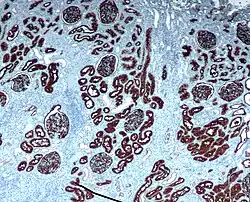

Immunohistochemical staining is widely used in the diagnosis of abnormal cells such as those found in cancerous tumors. In some cancer cells certain tumor antigens are expressed which make it possible to detect. Immunohistochemistry is also widely used in basic research, to understand the distribution and localization of biomarkers and differentially expressed proteins in different parts of a biological tissue.[4]

Reporter molecules vary based on the nature of the detection method, the most common being chromogenic and fluorescence detection. In chromogenic immunohistochemistry an antibody is conjugated to an enzyme, such as alkaline phosphate and horseradish peroxidase, that can catalyze a color-producing reaction in the presence of a chromogenic substrate like 3,3'-diaminobenzidine (DAB).[5] The colored product can be analyzed with an ordinary light microscope.[13] In immunofluorescence the antibody is tagged to a fluorophore, such as fluorescein isothiocyanate, tetramethylrhodamine isothiocyanate, aminomethyl Coumarin acetate or Cyanine5. Synthetic fluorochromes from Alexa Fluors is also commonly used.[13][14] The fluorochromes can be visualized by a fluorescence or confocal microscope.[13]

After immunohistochemical staining of the target antigen, another stain is often applied. The counterstain provide contrast that helps the primary stain stand out and makes it easier to examine the tissue morphology. It also helps with orientation and visualization of the tissue section. Hematoxylin is commonly used.[6][15]

Immunohistochemistry is an excellent detection technique and has the tremendous advantage of being able to show exactly where a given protein is located within the tissue examined. It is also an effective way to examine the tissues. This has made it a widely used technique in neuroscience, enabling researchers to examine protein expression within specific brain structures. Its major disadvantage is that, unlike immunoblotting techniques where staining is checked against a molecular weight ladder, it is impossible to show in immunohistochemistry that the staining corresponds with the protein of interest. For this reason, primary antibodies must be well-validated in a Western Blot or similar procedure. The technique is even more widely used in diagnostic surgical pathology for immunophenotyping tumors (e.g. immunostaining for e-cadherin to differentiate between ductal carcinoma in situ (stains positive) and lobular carcinoma in situ (does not stain positive)[19]). More recently, immunohistochemical techniques have been useful in differential diagnoses of multiple forms of salivary gland, head, and neck carcinomas.[20]